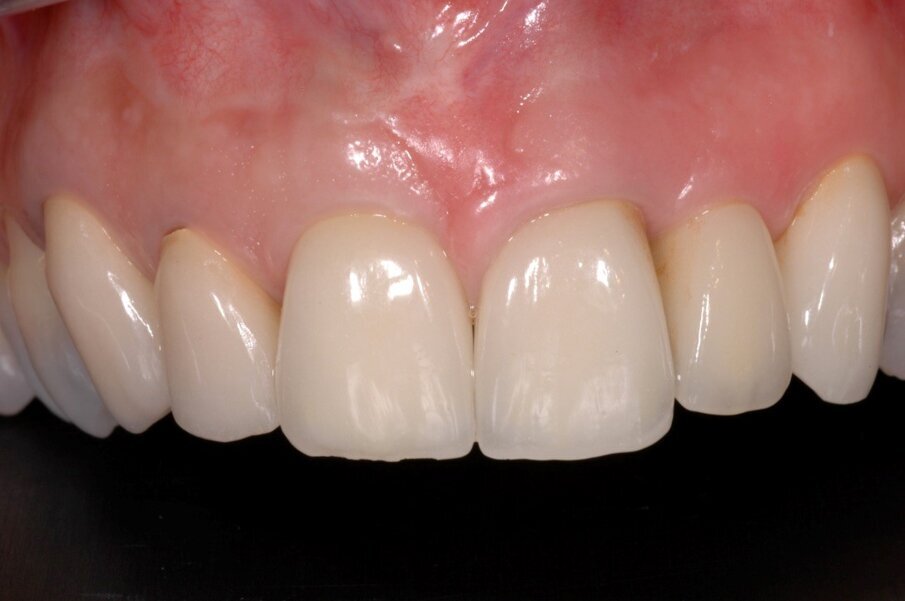

A questo punto veniva avvitato sull’impianto un moncone provvisorio, completato l’innesto di materiale biocompatibile con osso equino collagenato (OX granules, Bioteck) nel gap esistente tra la fixture e la lamina, poi veniva connessa al moncone provvisorio la corona provvisoria in resina (Fig. 13). La rx di controllo post intervento evidenzia la buona riuscita della procedura e la corretta connessione tra moncone e fixture (Fig. 14). Sei mesi più tardi alla rivalutazione e rimozione della corona provvisoria (Fig. 15) si può ben notare come questa procedura abbia permesso di mantenere integri i tessuti peri-implantari, di aver favorito la creazione di un tunnel mucoso spesso e maturo. I tessuti con e senza la corona provvisoria mostrano un aspetto naturale e le caratteristiche di una gengiva in salute (Figg. 16a, 16b).

La finalizzazione del caso ha previsto poi il rifacimento della vecchia corona su 12 insieme a quella su 11 in zirconia stratificata, progettata con il CAD/CAM, favorendo così il ripristino della funzione e dell’estetica laddove una complicanza aveva compromesso il risultato ottenuto dieci anni prima (Figg. 17-19). Sei mesi dopo l’intervento si può ben vedere come clinicamente e radiologicamente si sia ottenuto un buon successo bilogico ed estetico (Figg. 20-22).